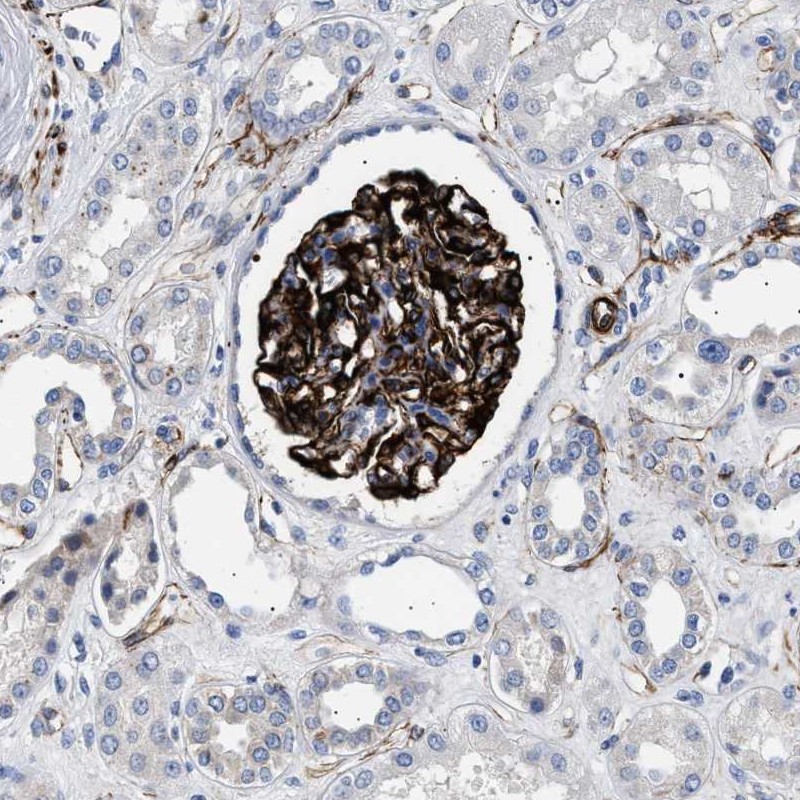

Immunohistochemical staining of human kidney shows strong cytoplasmic positivity in cells in glomeruli.